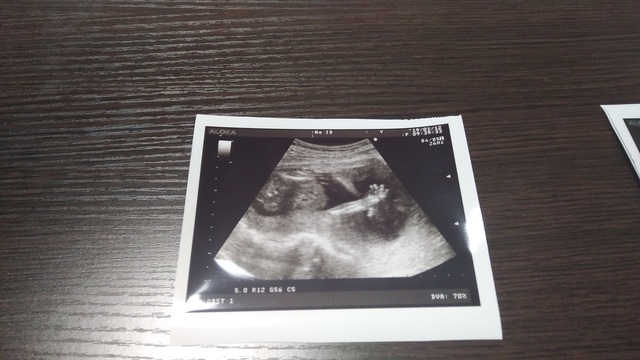

17週0日(17w0d・男の子)|Ayako. さん(32歳)

エコー写真撮影時のエピソード:

戌の日の安産祈願に行った時に周りの妊婦さんがかなりお腹が大きかったのに、私はお腹がなかなか大きくならずに心配していましたが、エコーの赤ちゃんはきちんと大きくなっていて安心できました。

右手をあげて、こちらに挨拶をしているようなポーズが面白くてお気に入りの一枚です。